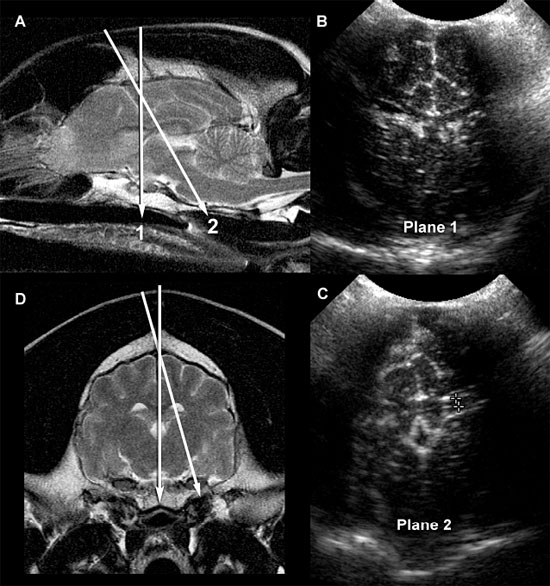

In young puppies, the bregmatic fontanel can be used as an acoustic window to the brain up to approximately 1 month of age (Hudson et al. 1991). In some individuals, particularly in toy-breed dogs, the bregmatic fontanels may persist into adult life. A kitten’s brain can be imaged through the fontanel up to about 5 months of age although accessibility decreases over time (Jäderlund et al. 2003). Unless the fontanel or defect is very large, the tip of the transducer must be held relatively stationary; the transducer can slide only a short distance. The brain is imaged by using a “windshield wiper” technique, with the tip of the probe acting as a pivot point to scan from rostral to caudal and back to obtain transverse images and from side to side to obtain longitudinal images. Because the probe is usually angled to view rostral and caudal structures, most images are made in oblique rather than perpendicular planes (Figure 1.1). Therefore, it should be remembered that, in rostral transverse images, ventral structures seen are actually located rostrally to dorsal structures in the image whereas, in the caudal transverse images, the ventral structures are located caudally to dorsal structures seen in the image.

Figure 1.1. Normal brain in a dog and ultrasound beams resulting in planes 1 and 2. A: Sagittal magnetic resonance image of the brain of a normal golden retriever illustrating how the ultrasound beam (planes 1 and 2 represented by the arrows) passes through the brain when the beam is placed over the fontanel to obtain transverse sonograms. B: Plane 1 shows the ultrasound beam angled perpendicular to the long axis of the brain to image the rostral horns of the lateral ventricles. C: Plane 2 shows the ultrasound beam angled caudally to image the third ventricle and mesencephalon. D: Transverse magnetic resonance image of the brain of a normal dog showing the axis of an ultrasound beam over the fontanel to obtain midline and parasagittal sonograms (arrows).